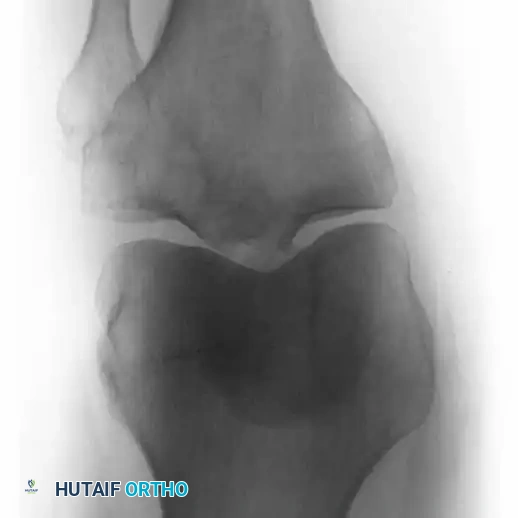

Fig. 22-21: (A) Osteonecrosis of the femoral head following radiation therapy for metastatic breast cancer. (B) Treatment with a cemented total hip arthroplasty. Because the host bone had been irradiated, both the femoral and acetabular components were cemented to ensure immediate and durable fixation.